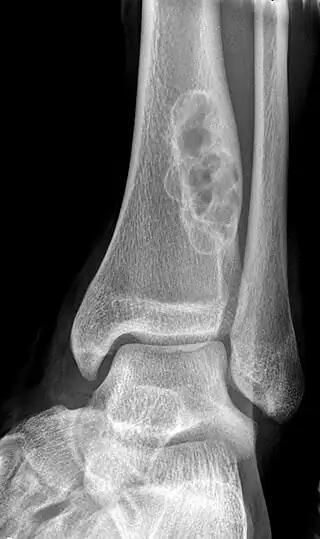

A bone tumor may be felt on examination, following which a plain X-ray is usually carried out.[4][13] Imaging is interpreted with the location of the lesion and the person's age being taken into account.[14]

X-ray appearances of different types of bone tumors in < 30 years.

X-ray appearances of different types of bone tumors in > 30 years.